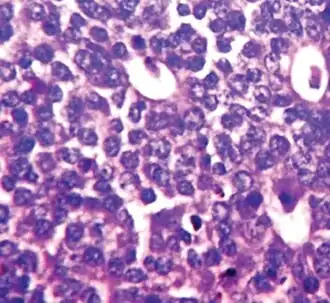

Nuclear pleomorphism

This parameter assesses whether the cell nuclei are uniform like those in normal breast duct epithelial cells, or whether they are larger, darker, or irregular (pleomorphic). In cancer, the mechanisms that control genes and chromosomes in the nucleus break down, and irregular nuclei and pleomorphic changes are signs of abnormal cell reproduction.

Note: The cancer areas having cells with the greatest cellular abnormalities should be evaluated.

- 1 point: nuclei with minimal or mild variation in size and shape

- 2 points: nuclei with moderate variation in size and shape

- 3 points: nuclei with marked variation in size and shape

-

Ductal carcinoma with mild nuclear pleomorphism. -

Invasive ductal carcinoma with moderate nuclear pleomorphism. -

Invasive lobular carcinoma with moderate nuclear pleomorphism. -

Invasive ductal carcinoma with marked nuclear pleomorphism.